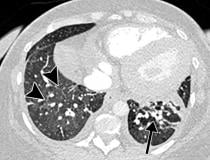

This photo gallery shows the variety of radiological presentations of COVID-19 (SARS-CoV-2) in medical imaging, including computed tomography (CT), radiograph X-rays, ultrasound, echocardiograms and magnetic resonance imaging (MRI). The radiology images show examples of typical COVID pneumonia in the lungs and the numerous complications the virus causes in the body in multiple organs, including the brain, kidneys, heart, abdomen and vascular system.